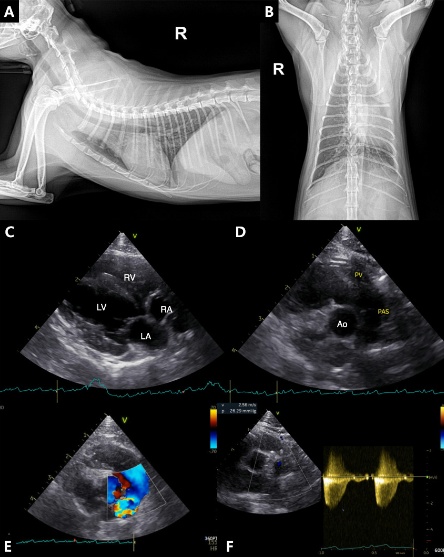

그러면서 면역매개성 사구체신염(ICGN), 변비, 요독증, CKD 관련 미네랄골질환(Mineral Bone Disorder) 등 삶의 질에 영향을 미치는 합병증의 진단과 치료 전략을 소개했다.

유 원장은 “여러 다양한 진단 도구를 활용해 최대한 빨리 진단해 관리해야 한다. 갑상샘기능항진증, 고혈압, 관절질환 등 병발질환에 잘 대응하는 것도 중요하다”고 강조했다.